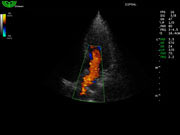

Система поддерживает СFM-режим, PW-режим, CW-режим, режим направленного энергетического потока, режим Color-M, панорамный режим, ECG, DICOM 3.0 и универсальные пакеты программ для кардиологии, сосудистого исследования и акушерства.

Режимы изображения: B, 2B, B/M, B/BC, CFM, PW, HPRF, PD, направленный PD, CW, режим Color M.

D3P64L 3.0МГц, фазированная решетка.

2.0МГц – 4.4МГц. Применения: кардиология, брюшная полость, акушерство. |